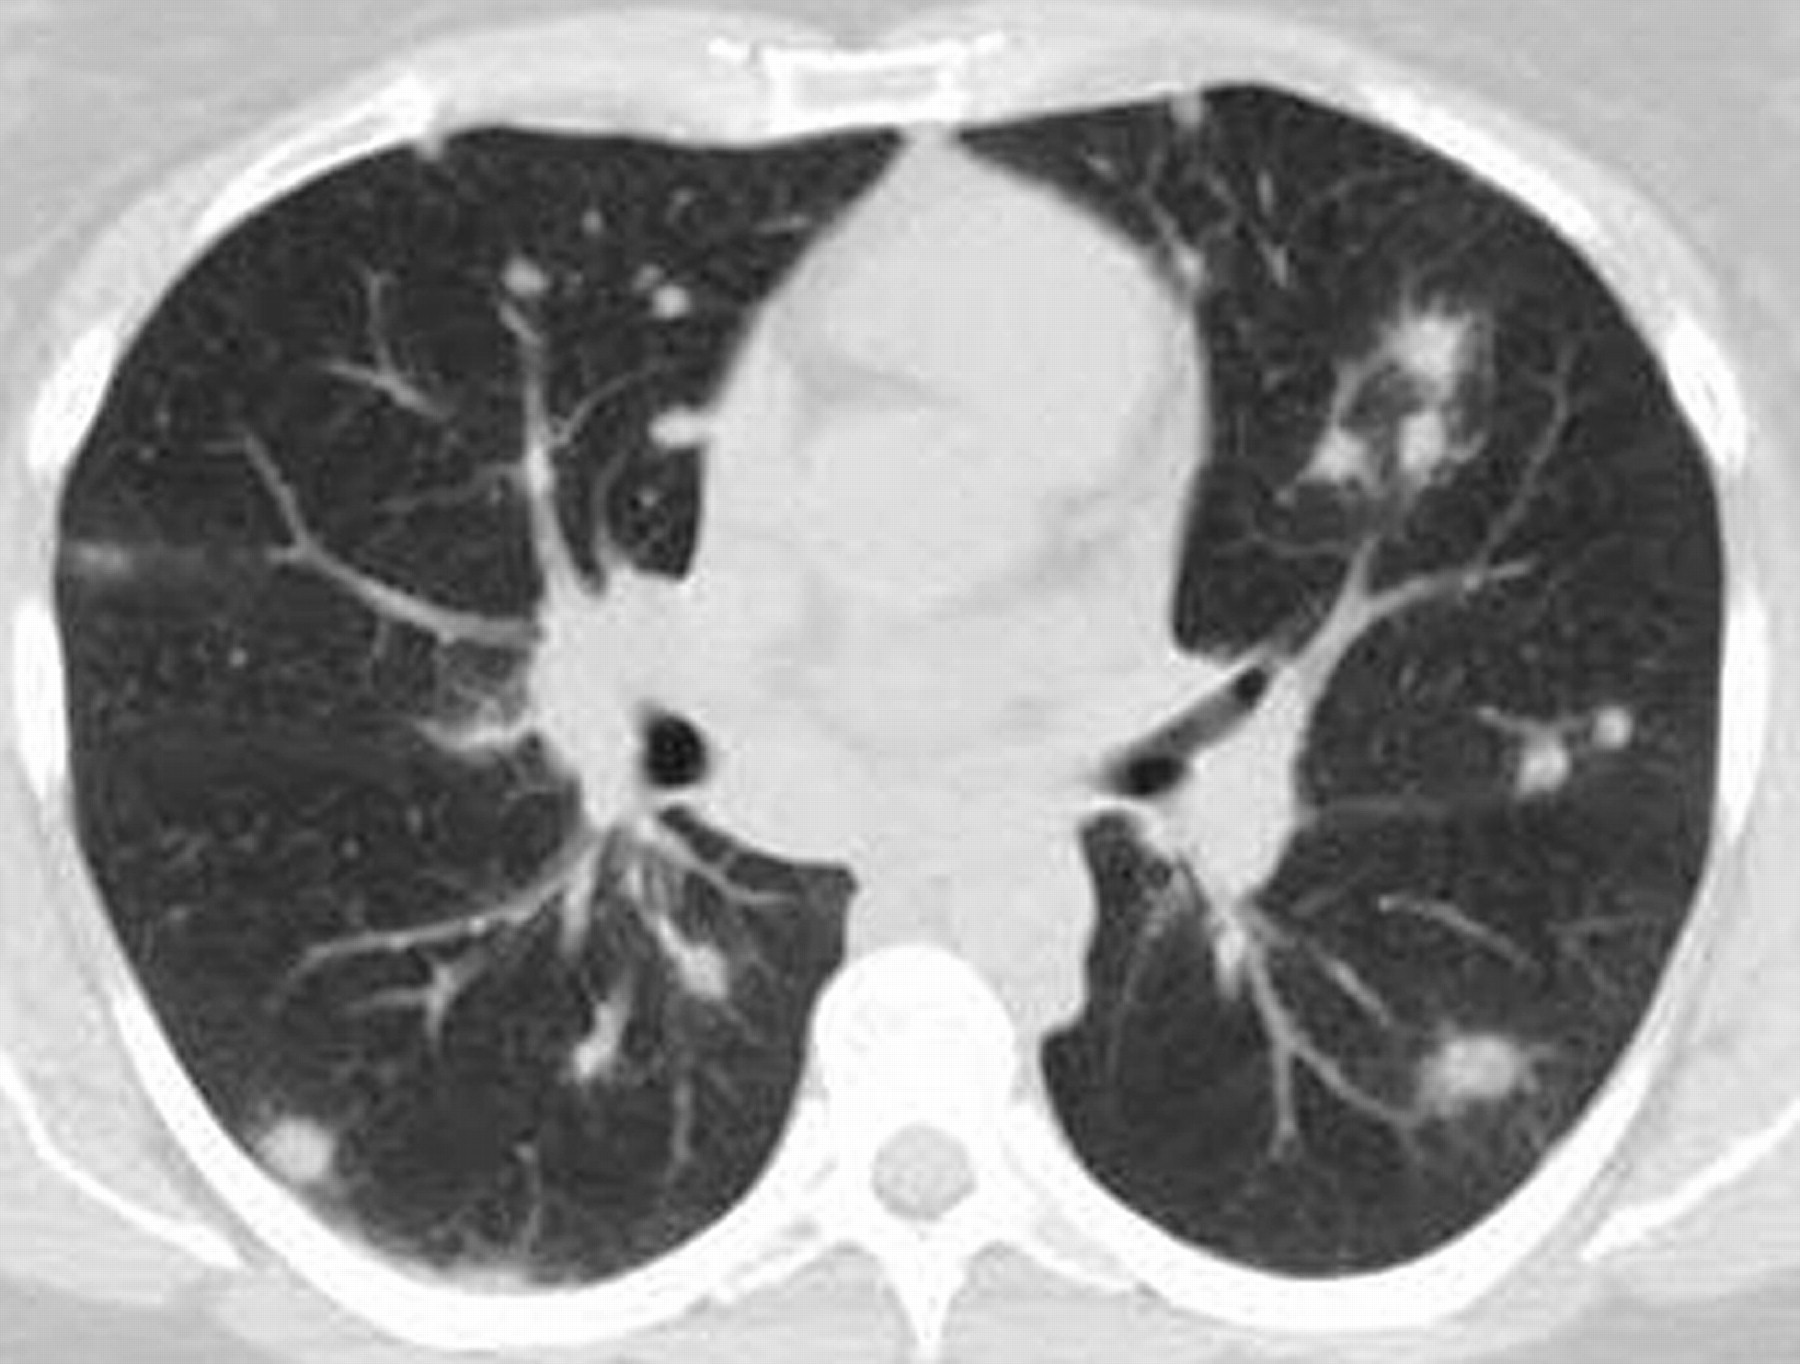

Η ακτινογραφία θώρακος δείχνει λεμφαδενοπάθεια με αποτιτανώσεις στο μεσοθωράκιο.

Αποτιτανώσεις στους πνεύμονες, τη σπλήνα και το ήπαρ, περικαρδίτιδα, πλευρίτιδα ή πλευριτική συλλογή.

Η ινώδης μεσοθωρακίτιδα προκαλεί στένωση των βρόγχων και των αγγείων του μεσοθωρακίου με αποτέλεσμα πνευμονική υπέρταση, σύνδρομο άνω κοίλης φλέβας και βρογχική απόφραξη.